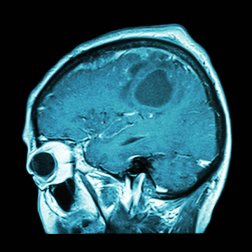

Será que teremos uma vacina contra o câncer no cérebro?

As vacinas são uma boa maneira de prevenir doenças, mas também permitem curá-las. Portanto, não é estranho que os pesquisadores estejam analisando diferentes possibilidades em suas tentativas de acabar com um câncer tão agressivo quanto o cerebral. Será que realmente é possível desenvolver uma vacina contra o câncer no cérebro?

Uma vacina contra o câncer no cérebro

No entanto, os pesquisadores descobriram que nem todos os tumores são iguais e nem todos respondem bem ao tratamento com imunoterapia. Por esse motivo, a “imunoterapia de precisão” foi trabalhada para tratar pacientes que sofrem de glioblastoma.

O glioblastoma é um dos cânceres com pior prognóstico. Portanto, os pacientes que estavam sofrendo com esta doença no momento do estudo precisavam de uma vacina personalizada para que os resultados fossem favoráveis. Qual foi o procedimento utilizado?